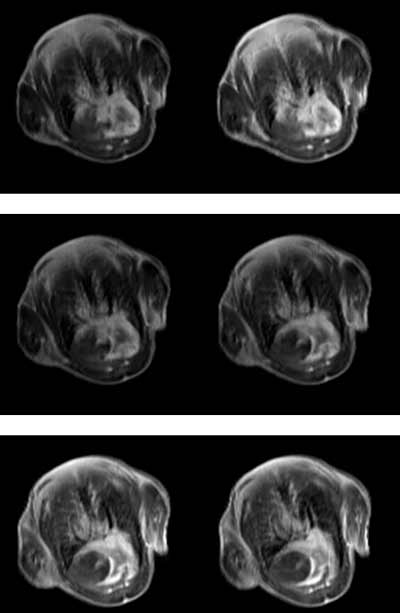

小鼠造影剂成像腹部成像数据

小鼠成像腹部成像数据